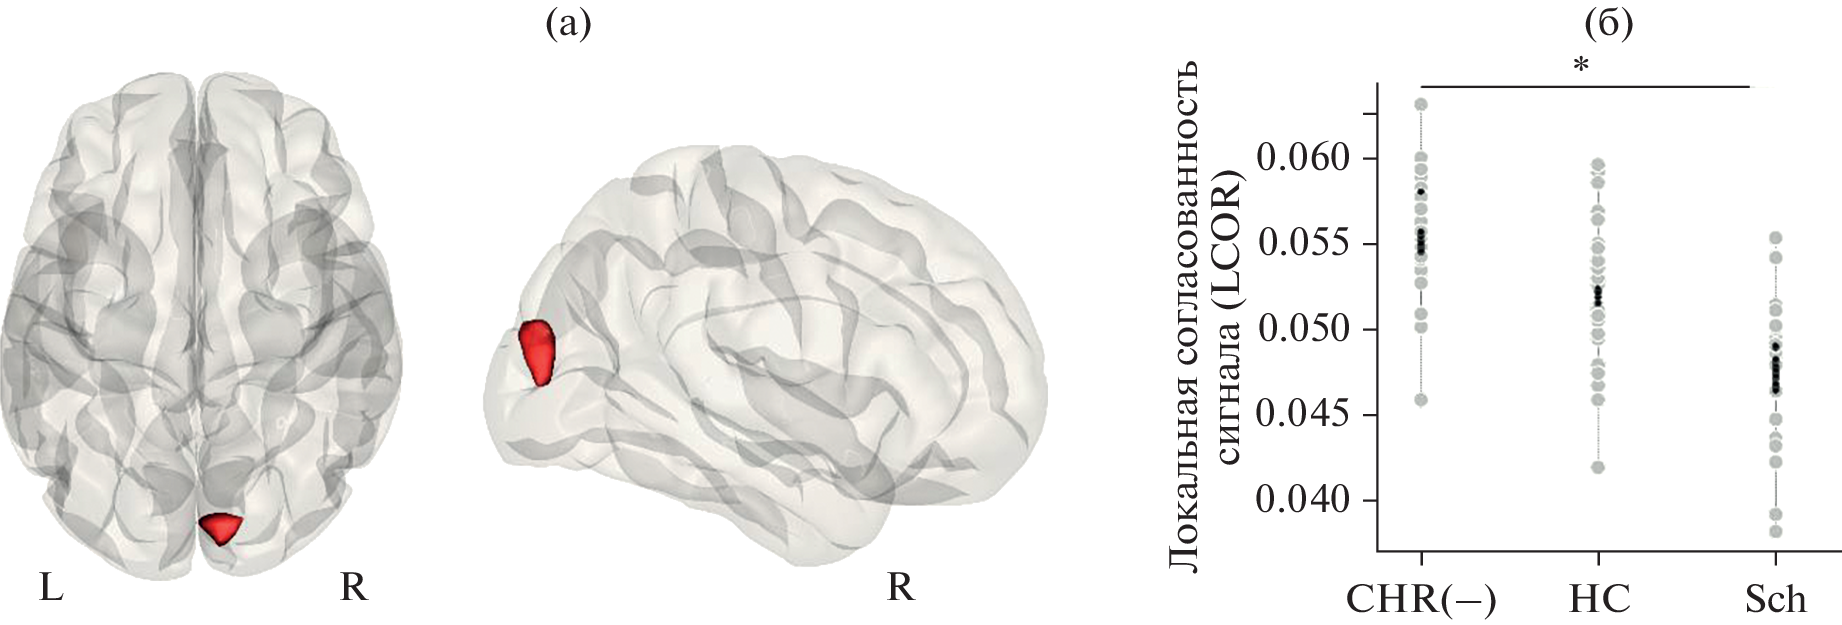

В рамках концепции “клинически высокого риска манифестации психоза” была поставлена цель выявления функциональных особенностей головного мозга (по данным фМРТ покоя) и нейропсихологических характеристик у 27 больных с непсихотическими психическими заболеваниями с аттенуированными симптомами шизофрении, психоз у которых не манифестировал в течение длительного периода наблюдения, по сравнению с 24 пациентами с первым эпизодом шизофрении и 27 психически здоровыми испытуемыми. Основная группа характеризовалась более высокой согласованностью BOLD-сигнала в зрительной коре правого полушария и большей функциональной связанностью между затылочным компонентом зрительной сети и компонентом сети определения значимости в правой префронтальной коре (по сравнению с больными шизофренией). В обеих группах пациентов было обнаружено снижение показателей продуктивности вербальных ассоциаций. Выявленные нейровизуализационные и нейропсихологические особенности пациентов основной группы можно рассматривать как отражение действия “защитных” и “патологических” механизмов при высоком риске манифестации шизофрении.